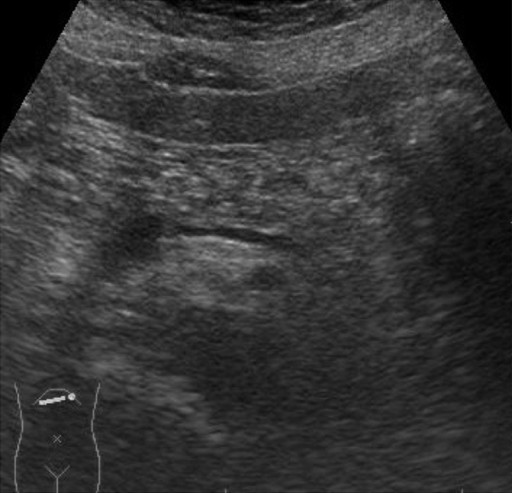

An esophagogastroduodenoscopy showed normal findings. Diseases such as reflux esophagitis and gastric ulcer were not observed. Ultrasonography (Figure 1) revealed a markedly heterogeneous pancreatic parenchyma demarcated from the neighboring tissues. The main pancreatic duct was not narrowed or dilated, and no tumor was detected. A CT image is shown in Figure 2. Plain CT (Figure 2a) revealed that the density of the pancreatic parenchyma had uniformly decreased to the same level as that of the surrounding fatty tissue. Contrast-enhanced CT (Figure 2b) revealed that the entire pancreatic parenchyma was absent and only a contrast-enhancing net-like shadow was visible. The magnetic resonance imaging (MRI) image is shown in Figure 3. The T1-weighted image could confirm that the entire pancreas was completely absent on T1-weighted images (fat suppression) (Figure 3). Endoscopic retrograde cholangiopancreatography (ERCP; Figure 4) showed no anomalous arrangement of the pancreaticobiliary ducts or pancreatic duct anomaly. Furthermore, obstruction, narrowing or dilatation of the main pancreatic duct was not observed. The branches of the pancreatic ducts appeared normal on the ERCP image. No abnormalities were observed in the bile duct.

Figure 1. Ultrasonography. The pancreatic parenchyma is markedly heterogeneous and demarcated from the neighboring tissues by a hazy borderline. The main pancreatic duct is not narrowed or enlarged, and no space-occupying lesion is visible. |